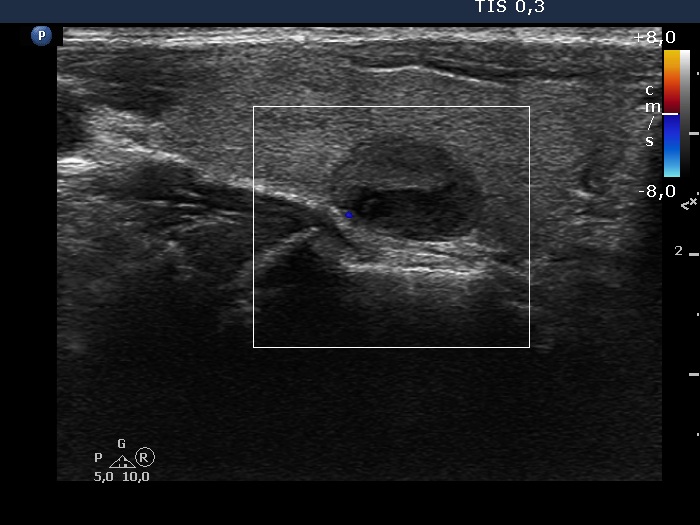

Right lobe, longitudinal scan

Right lobe, longitudinal scan, color Doppler mode. The heterogeneous nodule is also avascular.